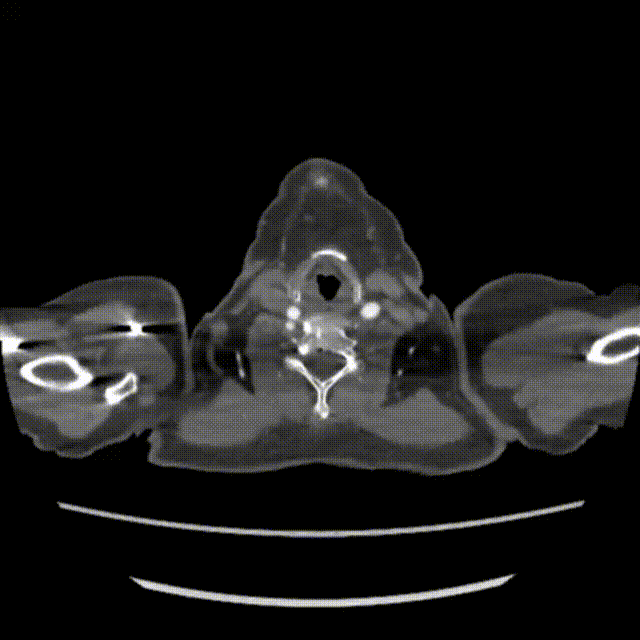

患者68岁,女性,5年于外院行腹主动脉瘤覆膜支架腔内修复术。5月前患者自觉背痛,于当地医院行CTA检查:符合腹主动脉及双侧髂总动脉支架置入术后。考虑左侧髂总动脉局部内漏并双侧髂总动脉水平壁间血肿可能。

二、术前CTA

术前主动脉CTA提示:左侧髂总动脉瘤样扩张,支架外见造影剂显影,瘤体内IMA开口水平亦可见造影剂显影,考虑左髂Ib型内漏合并IMA来源II型内漏可能。